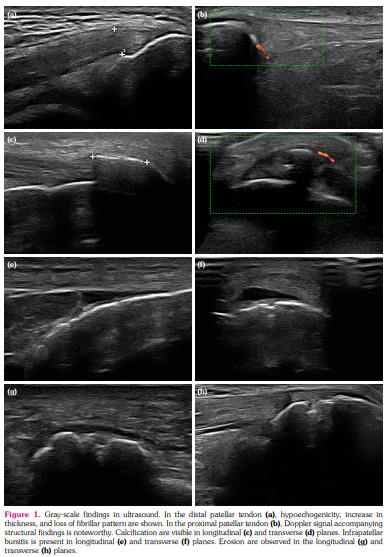

MASEI index evaluated five elemental lesions (scores) of enthesis: structure (0 or 1), thickness (0 or 1), erosions (0 or 3), calcifications (0, 1, 2, or 3), bursae (only at distal patellar tendon and Achilles tendon) (0 or 1), power Doppler signal (0 or 3).[22] Calcifications were scored as 0 if it was absent, 1 if <5 mm, 2 if 5-10 mm, or 3 if they were >10 mm.[23] Bursitis was defined as a compressible by the transducer, localized anechoic or hypoechoic, well-circumscribed area at Achilles enthesis and distal patellar enthesis. Erosion was defined as a cortical breakage with a step-down contour defect in two planes. A thickness assessment was made by measuring the maximal thickness at the bone insertion site. Based on enthesis-specific values (plantar aponeurosis >4.4 mm, Achilles tendon >5.29 mm, proximal and distal patellar tendon >4 mm, quadriceps tendon >6.1 mm, and triceps enthesis >4.3), it was determined whether there was an increase in thickness. Structural evaluation was defined as pathological in the presence of any of the loss of fibrillar pattern, hypoechoic appearance, and fusiform thickening in the enthesis area. The total score ranged from 0 to 136. The MASEI-Inflammatory score was recorded as entheseal thickness, structural changes, bursitis, and power Doppler findings, and MASEI-Damage score was recorded as calcifications and erosions (Figures 1, 2).[23]